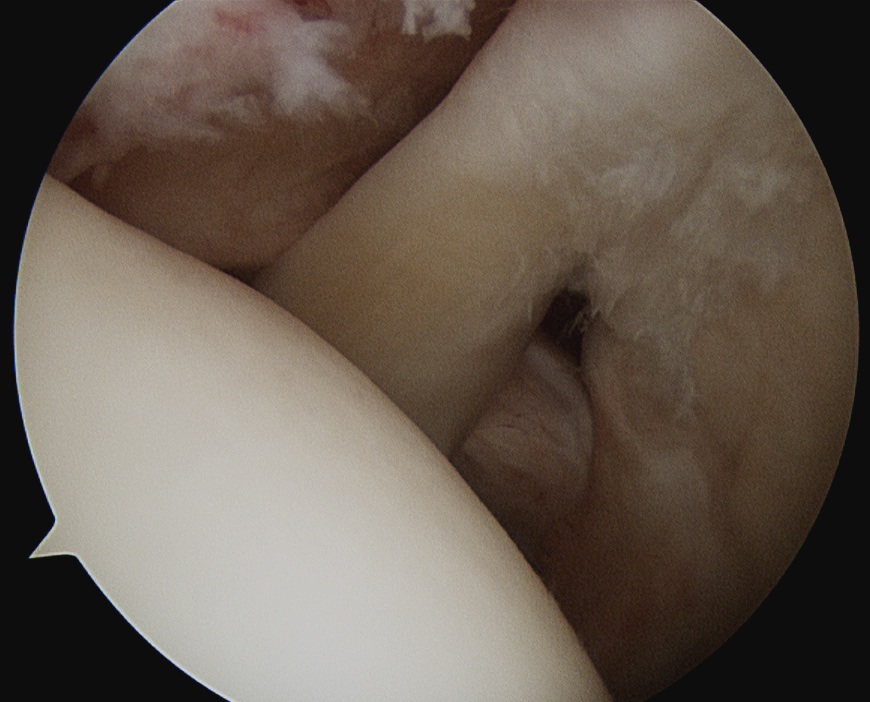

Medially dislocated biceps tendon with upper border subscapularis tear

Full thickness tear of subscapularis off insertion revealed with grasper